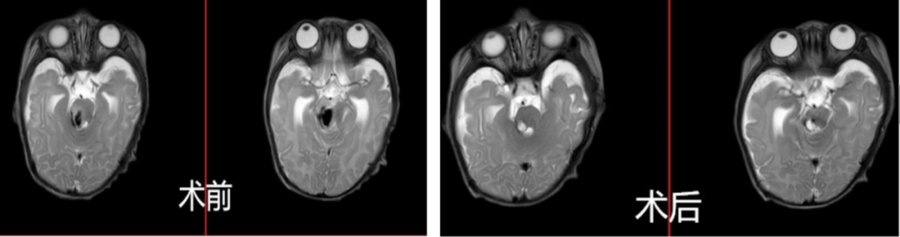

术前术后颅脑磁共振对比显示病变切除良好

在做好一切准备后,神经外科团队为甜甜安排了脑干海绵状血管瘤切除术,通过术中神经电生理监测充分保护面听神经功能,术中仔细分离病变与周围组织,完整切除病变,成功拆弹。

手术过程顺利,术中出血控制良好,仅仅输血0.5U,术中电生理监测提示手术前后比较无神经损伤加重表现,术后平稳转入重症监护室予以生命支持,术后第二天就成功脱离呼吸机,目前一般状态平稳。